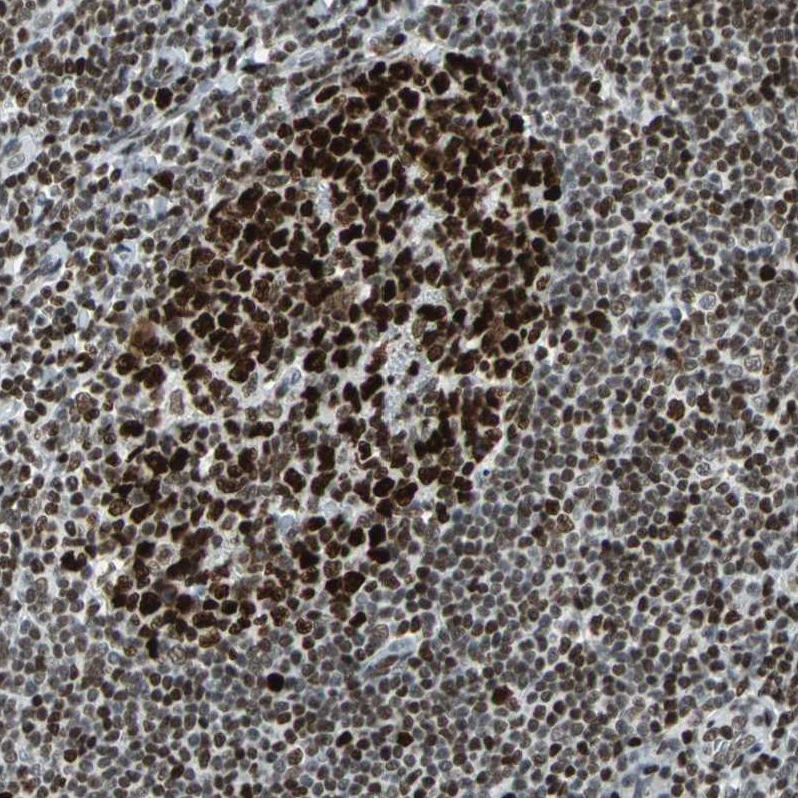

Immunohistochemical staining of human tonsil tissue shows strong nuclear positivity in non-germinal center cells and germinal center cells.